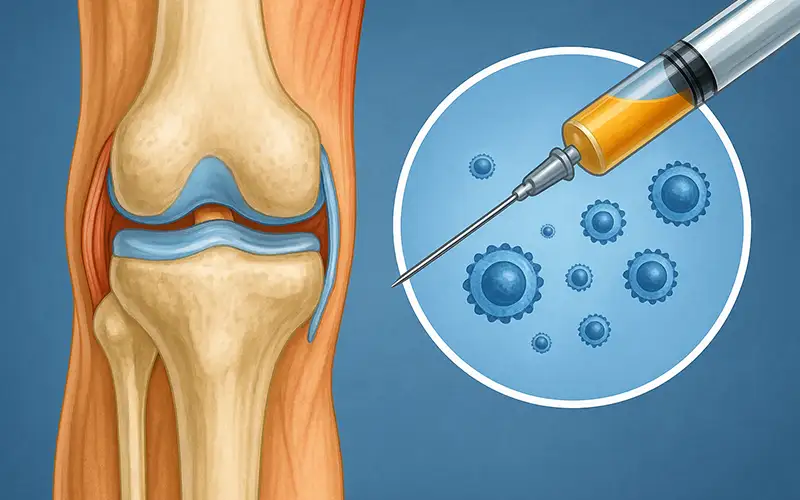

اگزوزوم تراپی یکی از جدیدترین روشهایی است که در حوزه پزشکی بازساختی مطرح شده و بهویژه در سالهای اخیر برای درمان آرتروز و دردهای مفصلی مورد توجه قرار گرفته است. این شیوه درمانی بر پایه استفاده از وزیکولهای بسیار ریز سلولی به نام اگزوزوم بنا شده است؛ ذراتی که نقش پیامرسانی بین سلولها را برعهده دارند و میتوانند پیامهای ترمیمی و ضدالتهابی را به بافتهای آسیبدیده منتقل کنند. با وجود جذابیت علمی و کاربردهای بالقوهای که برای این روش مطرح میشود، باید توجه داشت که اگزوزوم تراپی هنوز در مرحله تحقیقات اولیه قرار دارد و شواهد قطعی درباره اثربخشی بلندمدت آن محدود است.

در روش اگزوزوم تراپی، این ذرات پس از فرآوری، به صورت محلول آماده به داخل مفصل یا بافت مورد نظر تزریق میشوند. هدف از این تزریق، تقویت فرآیندهای طبیعی بدن برای ترمیم، کاهش التهاب و حمایت از سلولهای آسیبدیده است. این پیامرسانهای کوچک میتوانند باعث فعالسازی مکانیسمهای درونی ترمیمی در بافتها شوند و به همین دلیل در درمان مشکلات اسکلتیعضلانی توجه زیادی را به خود جلب کردهاند.

اگزوزوم تراپی در ارتوپدی برای کاهش التهاب، بهبود عملکرد غضروف، ترمیم آسیبهای بافت نرم و کمک به بازسازی مفاصل در آرتروز زانو و لگن در حال بررسی و مطالعه است.

اگزوزومها عمدتاً از سلولهای بنیادی مزانشیمی (MSC) یا منابع زیستی مشابه استخراج میشوند. پس از جمعآوری، طی مراحل مختلف خالصسازی، آمادهسازی و تست کیفیت، به صورت محلول تزریقی در اختیار پزشک قرار میگیرند. پزشک این محلول را به صورت مستقیم داخل مفصل یا بافت آسیبدیده تزریق میکند.

اگزوزومها پس از استخراج و خالصسازی از منابع سلولی، به صورت محلول آماده تزریق تهیه میشوند. پزشک این محلول را مستقیماً داخل مفصل یا بافت آسیبدیده تزریق میکند و هدف، تقویت فرآیندهای طبیعی ترمیم است.